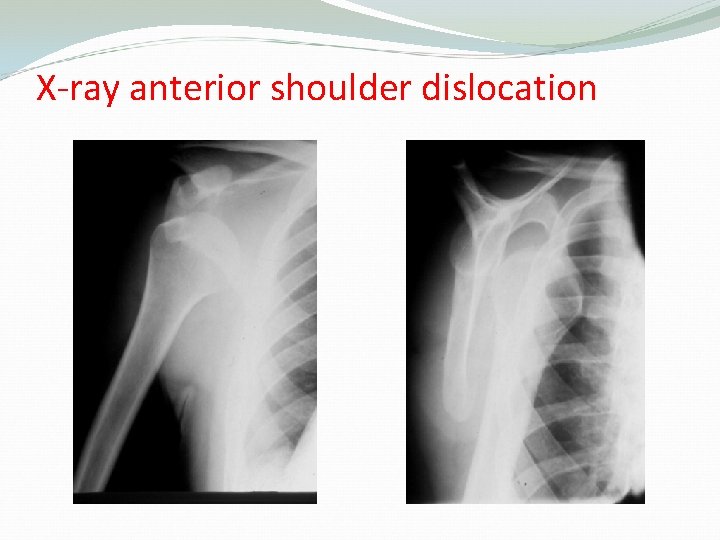

X-ray anterior shoulder dislocation